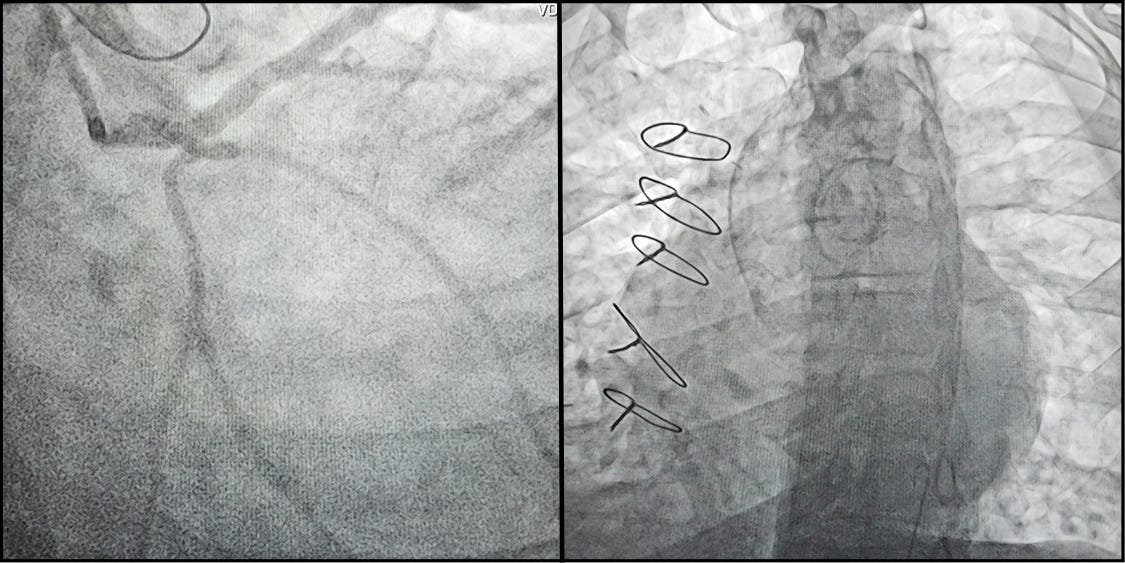

Imagem da semana - DESAFIO!

Paciente de 53 anos, submetido angioplastias e CRM com dupla mamária há 5 anos. Encaminhado devido a falha do resultado cirúrgico por oclusão da dupla mamária e presença de estenose aórtica importante.

CATE: lesão do óstio do TCE e CD proximal sem lesões distais.

Difícil, hein?! Resposta na próxima semana 😉.